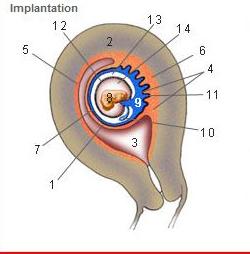

Where is the Desidua Capsularis?

1

Where is the Desidua basalis?

6

Where is the Desidua parietalis?

5

Where is the chorion frondosum?

11

Where is the amnion?

12

Where is the chorionic cavity?

13